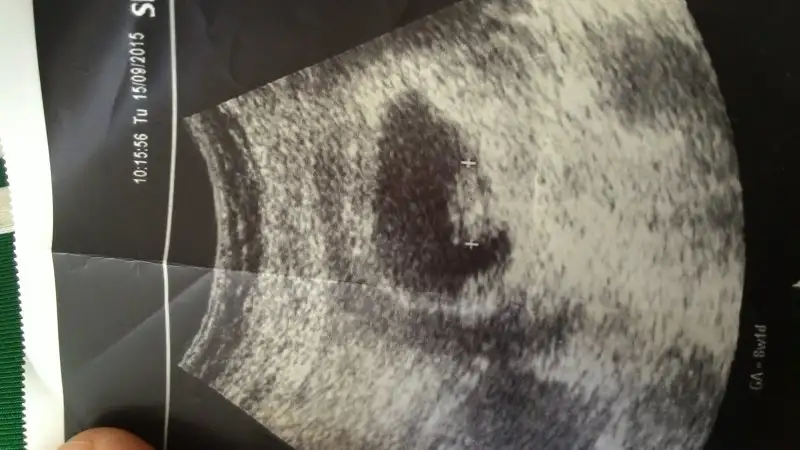

evet karından görüntü bu :) hayırlısı olsun sağlıklı olsun hepsi diyelim, tşk ettimm :)canım seninde solda. karından bakılan ultrason görüntüsüyse tabi. yani erkek oluyo bu durumda.

Peki benimki ne bu teoriye gore,karından baktı 7 haftalık fotoda bebek solda + işareti var bebegin olduğu yer

canım 8 haftalıkkene göre kıza daha yatkın gibi. ama ilkinde soldan çıkmış gibi ya. yoksa o yolk kesesi falanmı